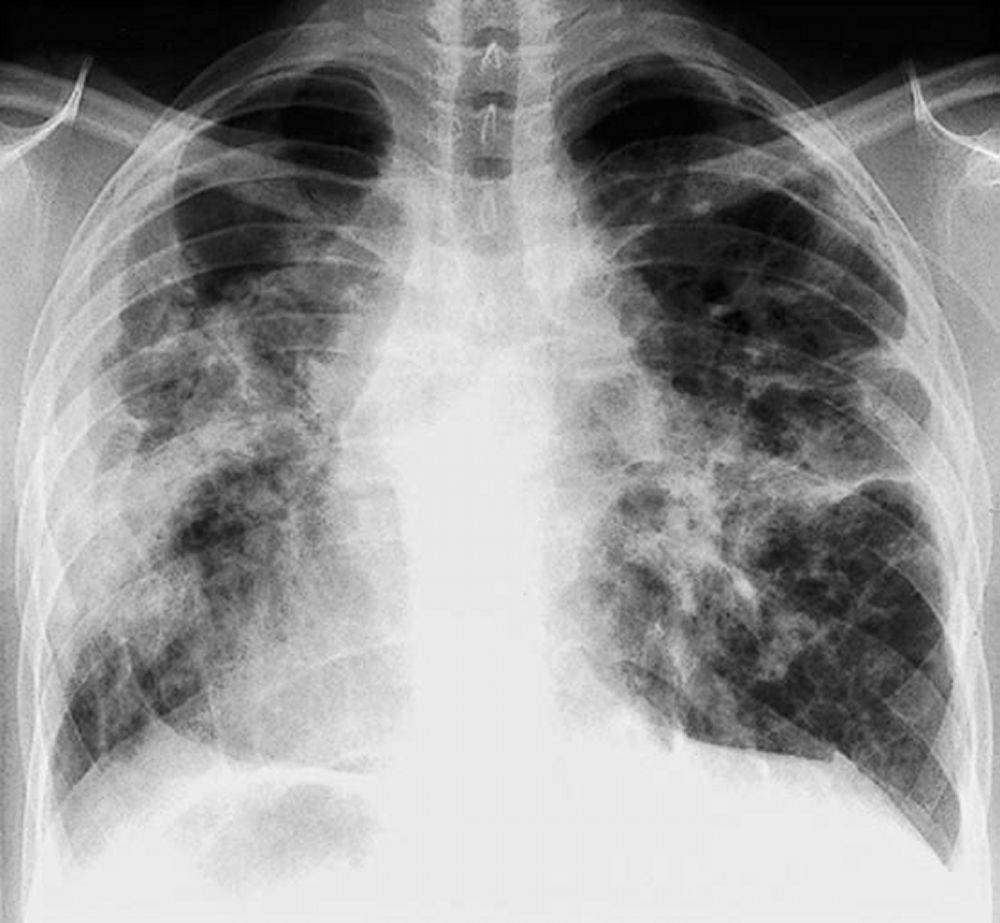

La radiografia del torace (RX) rimane il punto di partenza per la classificazione della sarcoidosi polmonare, utilizzando il sistema di Scadding che divide la malattia in quattro stadi principali sulla base dei reperti linfo-parenchimali.[1, 12, 13]

Tuttavia, la TC ad alta risoluzione (HRCT) è oggi considerata indispensabile per una migliore caratterizzazione. I segni tipici alla HRCT includono noduli a distribuzione perilinfatica (lungo i setti interlobulari e le scissure), ispessimento dei fasci broncovascolari e opacità a “vetro smerigliato” che riflettono un’alveolite granulomatosa attiva.